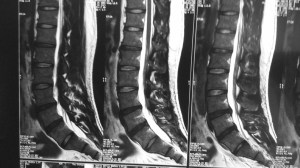

This is a patient who presented with sciatica in his left leg from a L5/S1 posterolateral left sided slipped disc in 2012.

He was offered surgery but chose conservative treatment.

His pain eventually resolved over a period of 3 to 6 months after taking medications and undergoing intensive physiotherapy.

The same patient underwent a new MRI scan of his lumbar spine in 2015 for lower backache. There was no sciatica in his lower limbs.

The MRI showed resorption of the previous large left sided slipped disc.